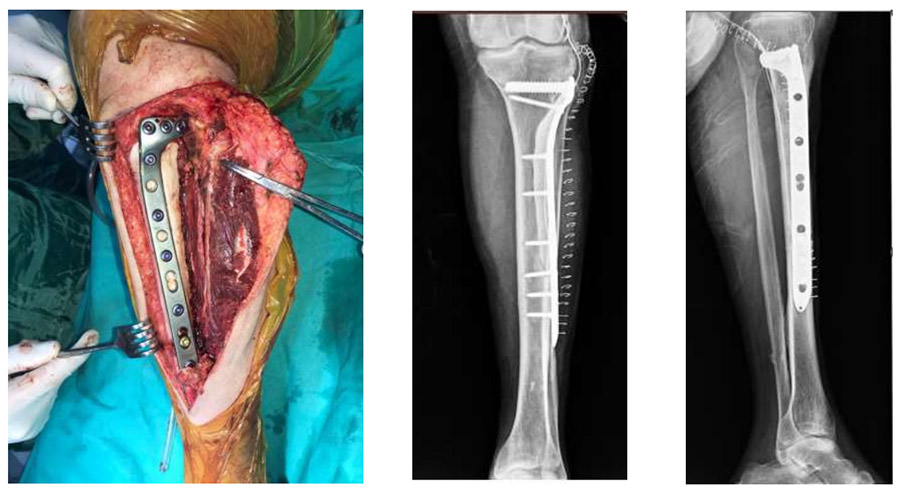

Ameliyat Esnası: Biyopsi traktını eksize edecek şekilde insizyon hattı, çıkarılan kitlenin klinik ve skopi görüntüsü görülmekte

Ameliyat Esnası ve Sonrası: Kitle çıkarıldıktan sonra çimento ve plak ile yapılan rekonstrüksiyonun klinik ve röntgen görüntüsü görülmekte